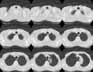

¥ Lung Cancer: Adenocarcinoma

8mmx4, Pitch 6, 384mm, 4-seconds, 150-mAs:

"High-speed screening mode."